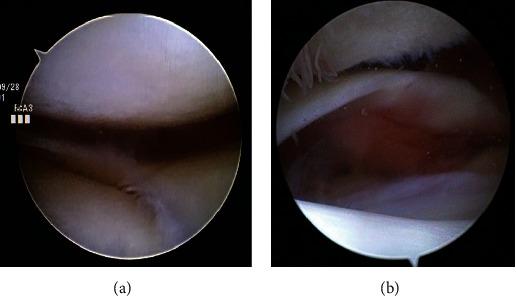

Posttraumatic patellar dislocation is rare, and consistent surgical strategy therefore has not been defined due to multifactorial factor. In this case study, we treated a case of a patellar dislocation with hip osteoarthritis and increased femoral anteversion by performing a two-staged surgery. In the first stage, total hip arthroplasty was performed, and in the second stage, simultaneous patellofemoral arthroplasty and medial patellofemoral ligament reconstruction using semitendinosus tendon autograft were performed. . A 56-year-old female patient who previously had right hip osteoarthritis complained of right knee pain after a fall. Radiographic examination showed lateral dislocation of the patella with osteoarthritic (OA) change in the patellofemoral joint and an excessive femoral anteversion with OA change on the right hip joint. Total hip arthroplasty was performed firstly to decrease femoral anteversion. Then, simultaneous patellofemoral arthroplasty and medial patellofemoral ligament reconstruction was performed for residual patellar dislocation and patellofemoral OA without tibiofemoral joint OA. At the time of the 5-year follow-up after surgery, the patient was able to walk with a wheelbarrow without any complications.

创伤后髌骨脱位较为罕见,由于多种因素,尚未确定一致的手术策略。在本病例研究中,我们通过两阶段手术治疗了一例伴有髋骨关节炎和股骨前倾角增大的髌骨脱位病例。第一阶段进行全髋关节置换术,第二阶段同时进行髌股关节置换术和使用半腱肌腱自体移植重建髌股内侧韧带。一名56岁女性患者,既往有右髋骨关节炎,跌倒后出现右膝疼痛。影像学检查显示髌骨外侧脱位,髌股关节有骨关节炎(OA)改变,右髋关节有股骨前倾角增大及OA改变。首先进行全髋关节置换术以减小股骨前倾角。然后,针对残留的髌骨脱位和髌股OA(无胫股关节OA),同时进行髌股关节置换术和髌股内侧韧带重建。术后5年随访时,患者能够使用轮椅行走,无任何并发症。